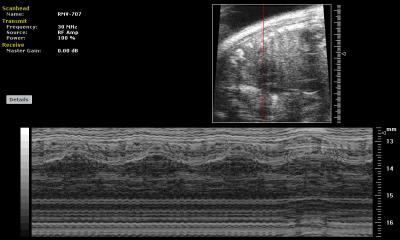

This ultrasound image shows a fetal mouse heart accompanied by an M‑mode Doppler reading of the heart rate.

UCSF